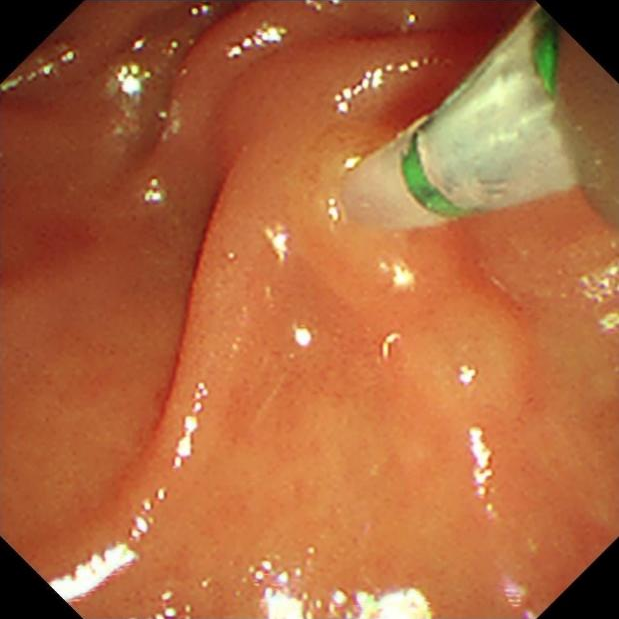

老家四川的小张(化名)是一名肺癌晚期患者,2023年10月,小张出现头晕,无法直线行走的情况,时间一长头晕的症状逐渐加重。 10月13日,小张在中国医学科学院肿瘤医院深圳医院的检查结果提示:脑膜转移。对应治疗后症状有所缓解。 11月16日,小张出现皮肤、巩膜发黄,抽血检验提示胆红素进行性升高,考虑为梗阻性黄疸。 胆总管是胆汁唯一的出路,当胆总管出现梗阻时,胆汁没有排出的通道,就会出现腹痛、发热、黄疸等情况。 这条“生命通道”一旦被完全堵死,极易发展为化脓性胆管炎、感染性休克、脓毒血症等情况,随时危及生命。 该技术是目前微创治疗胆胰疾病的主要手段之一,整个手术耗时仅40分钟。术后复查,小张胆红素指标明显下降。 ERCP技术具有创伤小,病程短,疗效好,并发症少等优点,目前医院已能熟练开展该项技术,内镜科也在解决胆道、胰腺系统急危重症方面有了新的突破,为患有胆胰系统疾病的患者带来福音。 内镜逆行胰胆管造影术(ERCP)是指医生将十二指肠镜经口插至十二指肠降部,找到十二指肠乳头,经十二指肠乳头导入专用器械进入胆管或胰管内,在X线透视或摄片下注射显影剂造影、导入经口胰胆镜/超声微探头观察、进行胆管刷检/活检获取病理标本等操作,完成对胆胰系统疾病的诊断,并在诊断的基础上实施相应介入治疗技术的总称,是国际公认的胆道、胰腺系统疾病诊断的金标准。 胆道梗阻引起的黄疸 临床实验室或影像学检查,支持胰腺或者胆道的疾病,包括结石、肿瘤、硬化性胆管炎等 胰腺相关疾病,包括胰腺肿瘤、慢性胰腺炎、胰腺脓肿等 原因不明的胰腺炎 奥迪氏括约肌病变 胰管或者胆管的组织活检 内镜下逆行胰胆管造影术、内镜下鼻胆管引流术、内镜下乳头括约肌切开术、内镜下胆管支架植入术、内镜下胰管支架植入术、内镜下胆管结石取石术、内镜下胆管扩张术、内镜下乳头括约肌球囊扩张术等。 以上ERCP技术,可满足梗阻性黄疸、胆道结石、胆管/胰管狭窄等常见胆胰系统疾病的诊治。